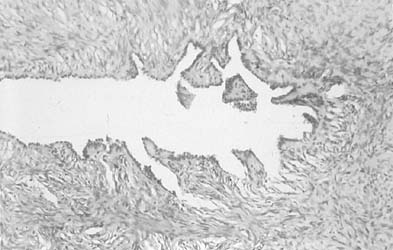

To understand the histogenesis of intraepithelial neoplasia and invasive carcinoma, knowledge of some basic morphologic concepts is necessary (see Fig. 9). The endocervical canal is composed of tall columnar ciliated and nonciliated and mucus-producing cells. Normally, the endocervical epithelium is attached directly to the stroma without a basal layer. Under the mucosa, there are isolated immature totipotential cells that are the source of development of the endocervical cells. Under a variety of hormonal or physical stimuli, these germinative cells may proliferate, giving rise to reserve cell hyperplasia (Fig. 10). Reserve cell hyperplasia may develop in young patients as a result of physical injury and in postmenopausal patients because of hormonal stimuli, or from hormones produced by the adrenal gland that are later metabolized to estrone.66 The cells desquamated from reserve cell hyperplasia have small nuclei, finely granular chromatin, and small amounts of cytoplasm. Caution should be taken not to overdiagnose them as CIS in cytologic and histologic samples. They have a monomorphic appearance, do not display hyperchromasia, and usually are seen in organized small clusters (see Fig. 10). A neoplastic process may develop in those cells as CIS of the small cell type (Fig. 11) and, later, as small cell invasive carcinoma (see Fig. 9 and Fig. 12). Small cell undifferentiated squamous CIS is seen as small cells with hyperchromatic nuclei with limited amounts of cytoplasm. To a certain extent, the features of invasive small cell carcinoma are similar to those of the intraepithelial form. However, tumor diathesis, that is necrosis, hemolyzed blood, and cellular debris, and enlarged nucleoli frequently are associated with the invasive type.

Fig. 10. Histologic section showing reserve cell hyperplasia and squamous metaplasia of the endocervix (Hematoxylin and eosin, × 260). Inset. Reserve cell hyperplasia and squamous metaplasia of the endocervix. The cells are small and monomorphic, with finely distributed chromatin.(Papanicolaou, × 360).